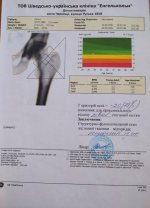

Вже зібрали 47 718 гривень, а потрібно 205 000 гривень. Першу операцію зробили в місті Чернівці у шведсько-українській клініці «Енгенхольм» 24 березня 2021 року. Наступну можна робити через три місяці — 24 червня.

Попереду Олега очікує дороге ендопротезування одного кульшового суглоба (одна операція, після якої має відбутись курс реабілітації).